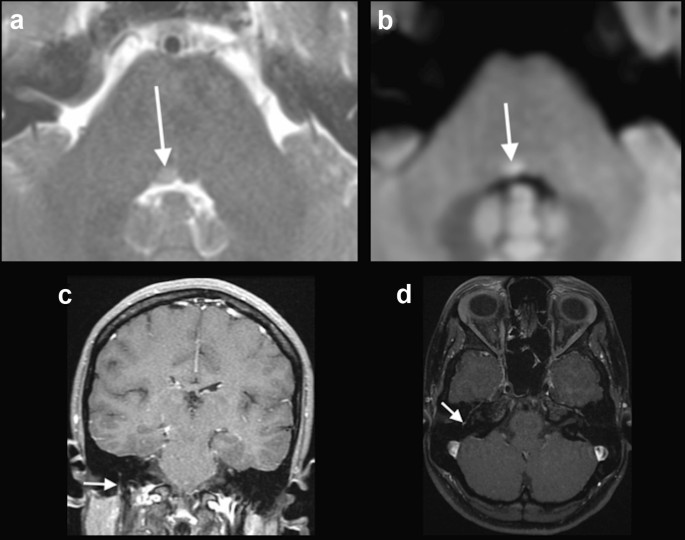

Fig. 3

figure 3

COVID-19 associated with right facial and abducens nerve palsy. Brain MRI demonstrated a discrete hyperintense focus on T2-weighted imaging in the right abducens nerve nucleus (arrow in a), associated with restricted diffusion (arrow in b). MRI also revealed gadolinium enhancement in the mastoid portion of the right facial nerve, on T1-weighted spin-echo imaging (arrows in c) and on T1-3D MPRAGE (arrow in d). Although enhancement in the mastoid segment of the facial nerve can occur secondary to physiological circumneural venous plexus, this finding was asymmetrical, and correlated with the clinical symptoms

Case 4: A 30-year-old previously healthy woman presented with mild fever and sore throat. A nasopharyngeal swab was positive for SARS-CoV-2, after 5 days presenting symptoms. Ten days after the initial symptoms, she presented with right facial nerve palsy. Brain MRI, performed 4 days after, showed gadolinium enhancement in the canalicular portion of the right facial nerve and in the right geniculate ganglion (Fig. 4). The patient presented complete recovery after 5 days of treatment with oral prednisone, 60 mg/day.

Fig. 4

figure 4

COVID-19 associated with right facial nerve palsy. MRI demonstrated gadolinium enhancement in the canalicular portion of the right facial nerve (arrows) and geniculate ganglion, on T1-weighted spin-echo imaging